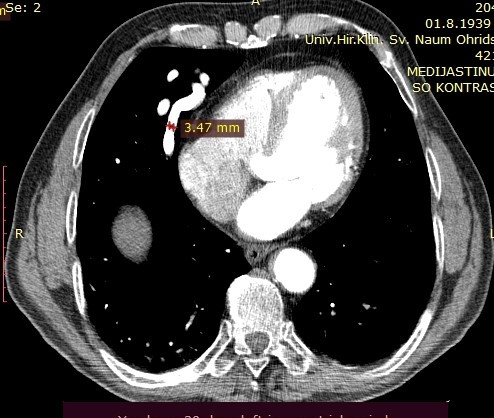

On the performed lung MDCT in the arterial phase, a fistula connecting arterial to venous vessels is clearly demarcated, with bridging of the normal capillary bed between them. The arterial blood vessel measures 3.47mm in diameter and may be a candidate for coil embolization.

Image 3. MDCT of the lungs, arterial phase, showing the pulmonary artery with a diameter of 3.47mm.